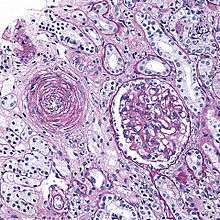

"Onion-skin" renal arteriole

Hyperplastic arteriolosclerosis is a type of arteriolosclerosis involving a narrowed lumen.[1]

The term "onion-skin" is sometimes used to describe this form of blood vessel[2] with thickened concentric smooth muscle cell layer and thickened, duplicated basement membrane. In malignant hypertension these hyperplastic changes are often accompanied by fibrinoid necrosis of the arterial intima and media. These changes are most prominent in the kidney and can lead to ischemia and acute kidney failure.